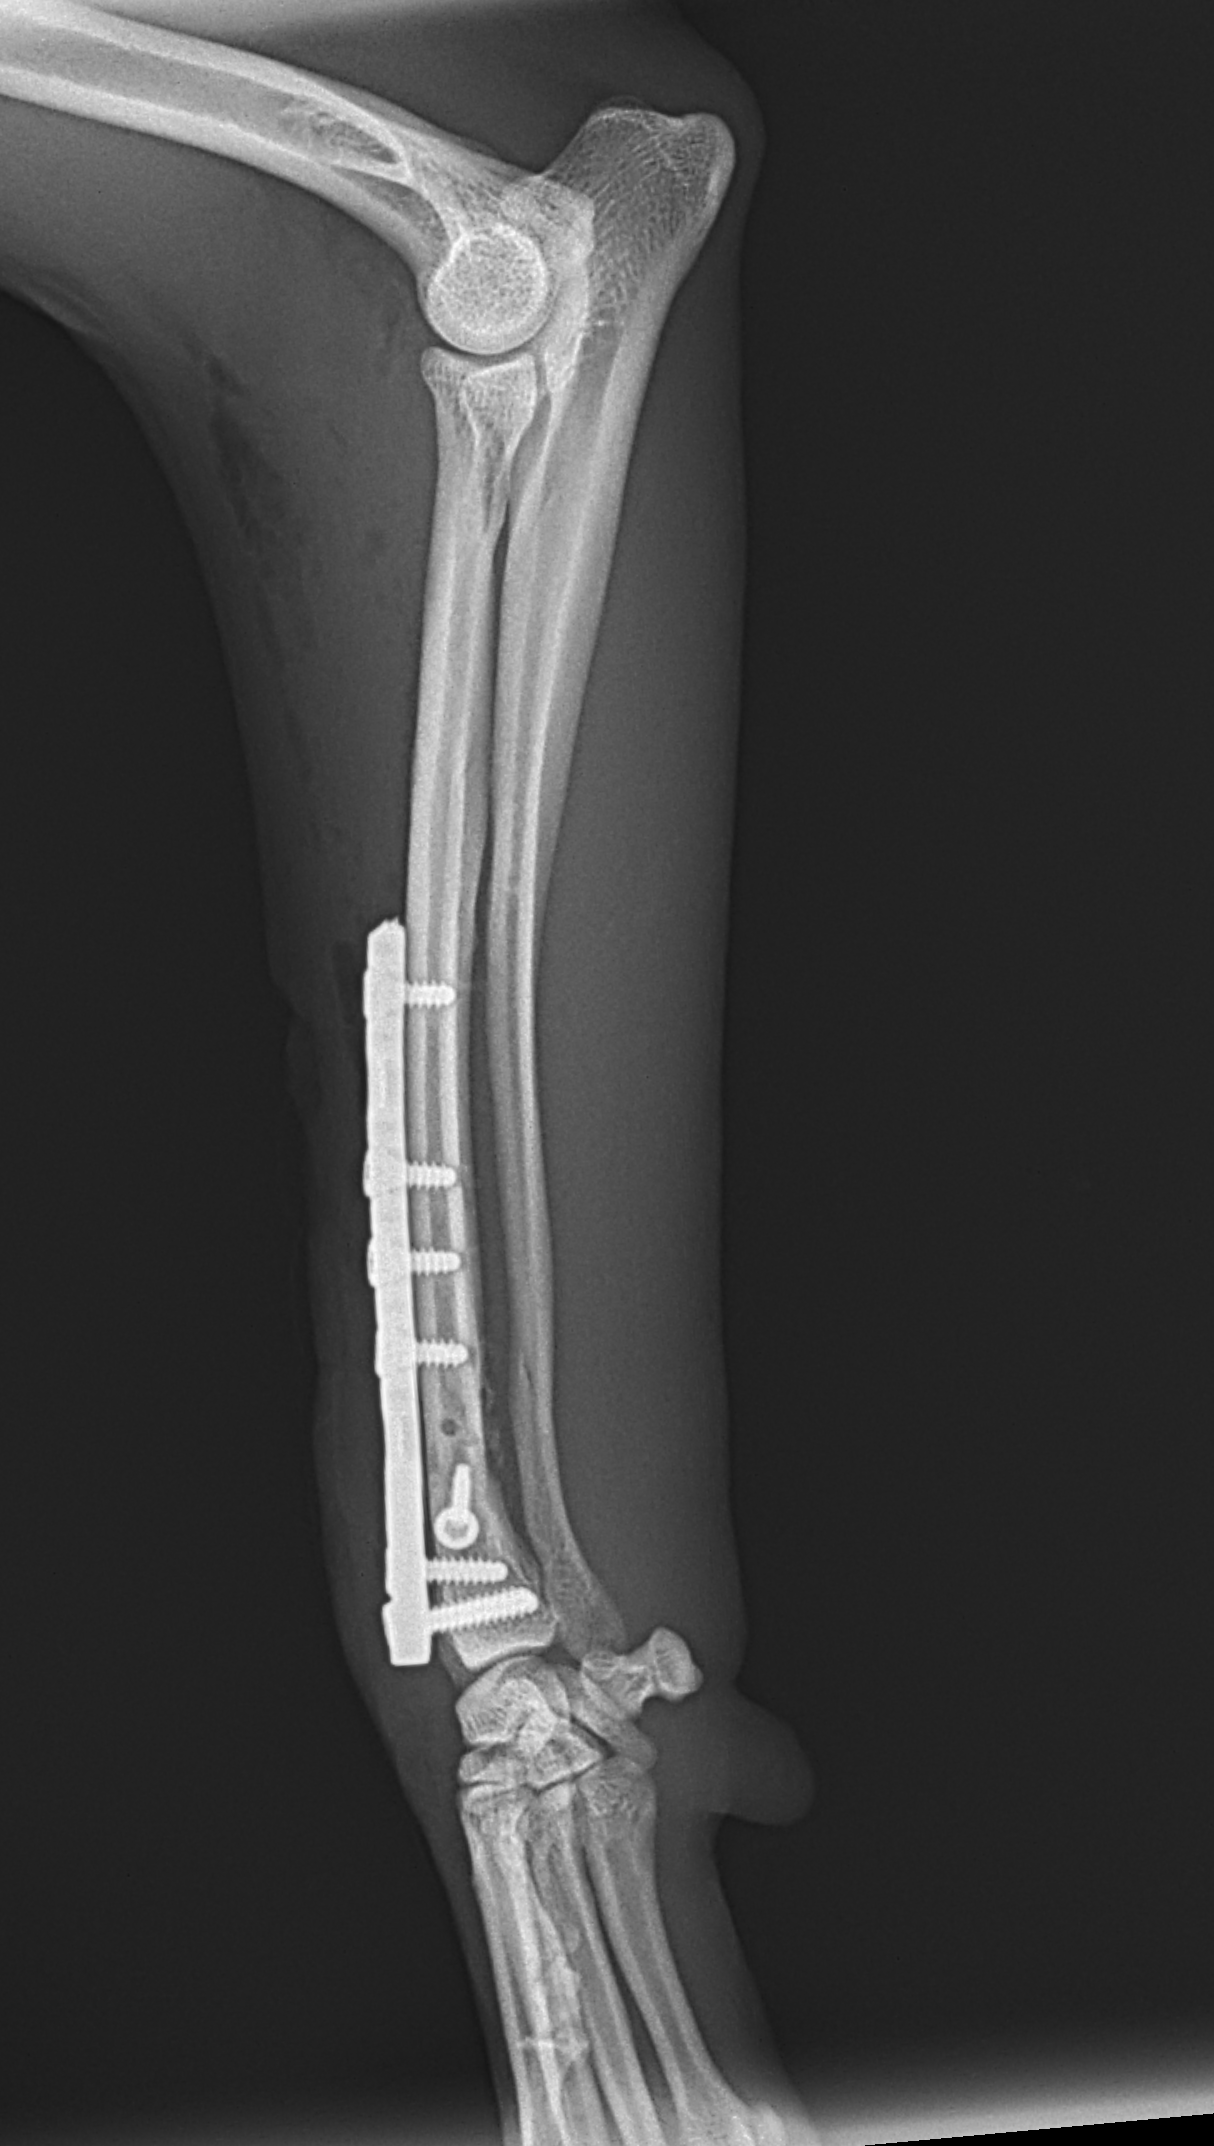

橈骨固定術 #266 6歳のワンコが落下事故により橈骨骨折をしたとの事。関節近傍から斜骨折をしています。1.5のPosition Screw、2.0 TH Plateで固定術を行いました。しばらくは安静が必要です。 症例カテゴリー 放射線治療整形外科軟部組織外科脳神経外科内科腫瘍外科救急・集中治療リハビリテーション科腫瘍内科内視鏡科脳神経科呼吸器外科中医・漢方猫の腎移植循環器科